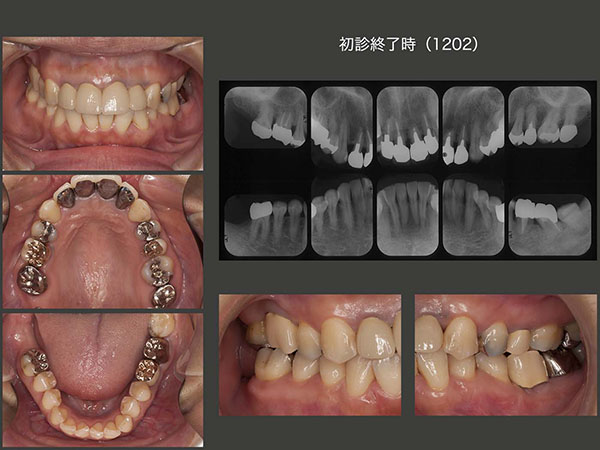

2009年7月初診,38歳女性.右上および左下の欠損の治療ならびに前歯の隙間が気になるという主訴で来院.上顎前歯は10年前イタリア留学中に製作したとのこと.全体に軽度の歯周病がみられた.特に左下7の遠心に10mmの歯周ポケットあり,この結果左下⑤6⑦のブリッジは難しいと判断した.

2009年11月,機能していない右上7を抜歯し,左下6部に移植した.隣在歯の右上7が移動したため,近心傾斜している右上6のアップライトが可能となり,出来上がったスペースに,やはり非機能歯である右下8を移植した.この際,ドナー歯(大臼歯)が,顎堤(受容側・小臼歯部))より大きかったので,骨片を挿入し血餅の保持に努めた.(今なら,頰側骨の拡大を行うが,当時は手技が未熟であった.)